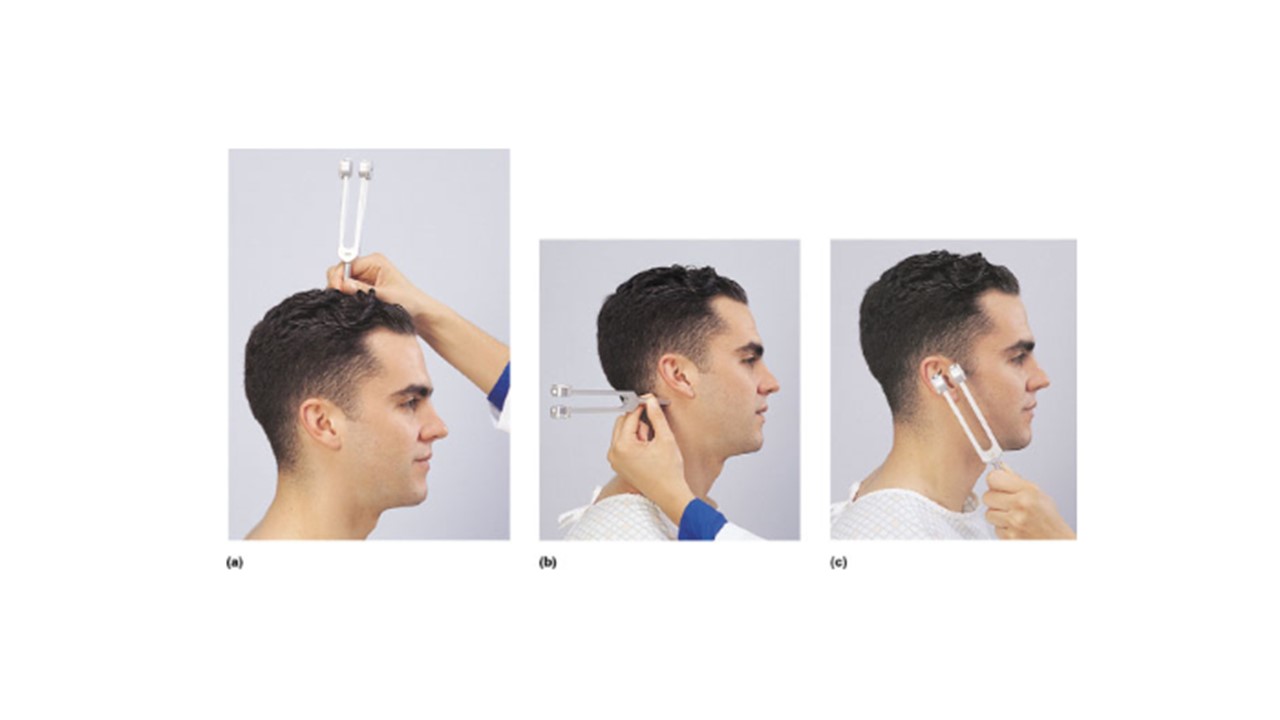

Which lettered image(s) above demonstrates the proper administration of the Weber Test?

a

If the man in image a hears the tone in his left ear but not his right he is experiencing __________________ deafness in his right ear.

sensorineural